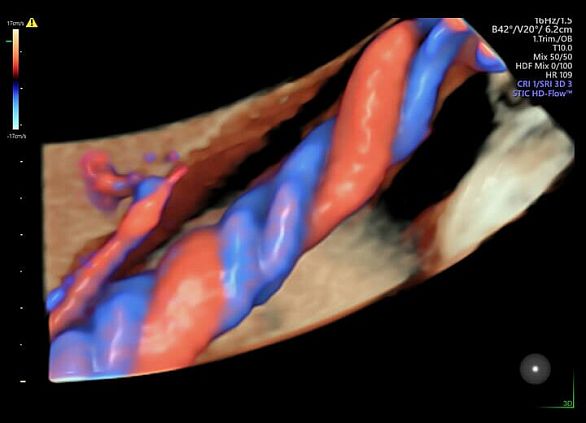

Клинические изображения

- Программа 3D и режим инверсии (при наличии специализированных датчиков).

- HDlive — экстраординарная технология рендеринга, создающий удивительно реалистичные объемные изображения плода.

- Программа 3D и режим инверсии (при наличии специализированных датчиков).

- HDlive — экстраординарная технология рендеринга, создающий удивительно реалистичные объемные изображения плода.

3D/4D УЗИ в ежедневной практике

Объемные ультразвуковые исследования являются неотъемлемым частью современной диагностики в сфере Женского здоровья. Благодаря передовым технологиям формирования УЗ луча и широким возможностям сканирования Voluson E6 обеспечивает получение 3D/4D изображений с исключительным анатомическим реализмом, что позволяет уверенно решать самые сложные клинические задачи.

- HDlive — технология формирования реалистичных ультразвуковых изображений. Она позволяет увеличить глубину восприятия, упрощая оценку анатомии и облегчая пространственное интерпретацию исследуемых структур, что придает уверенность в принятии клинических решений.